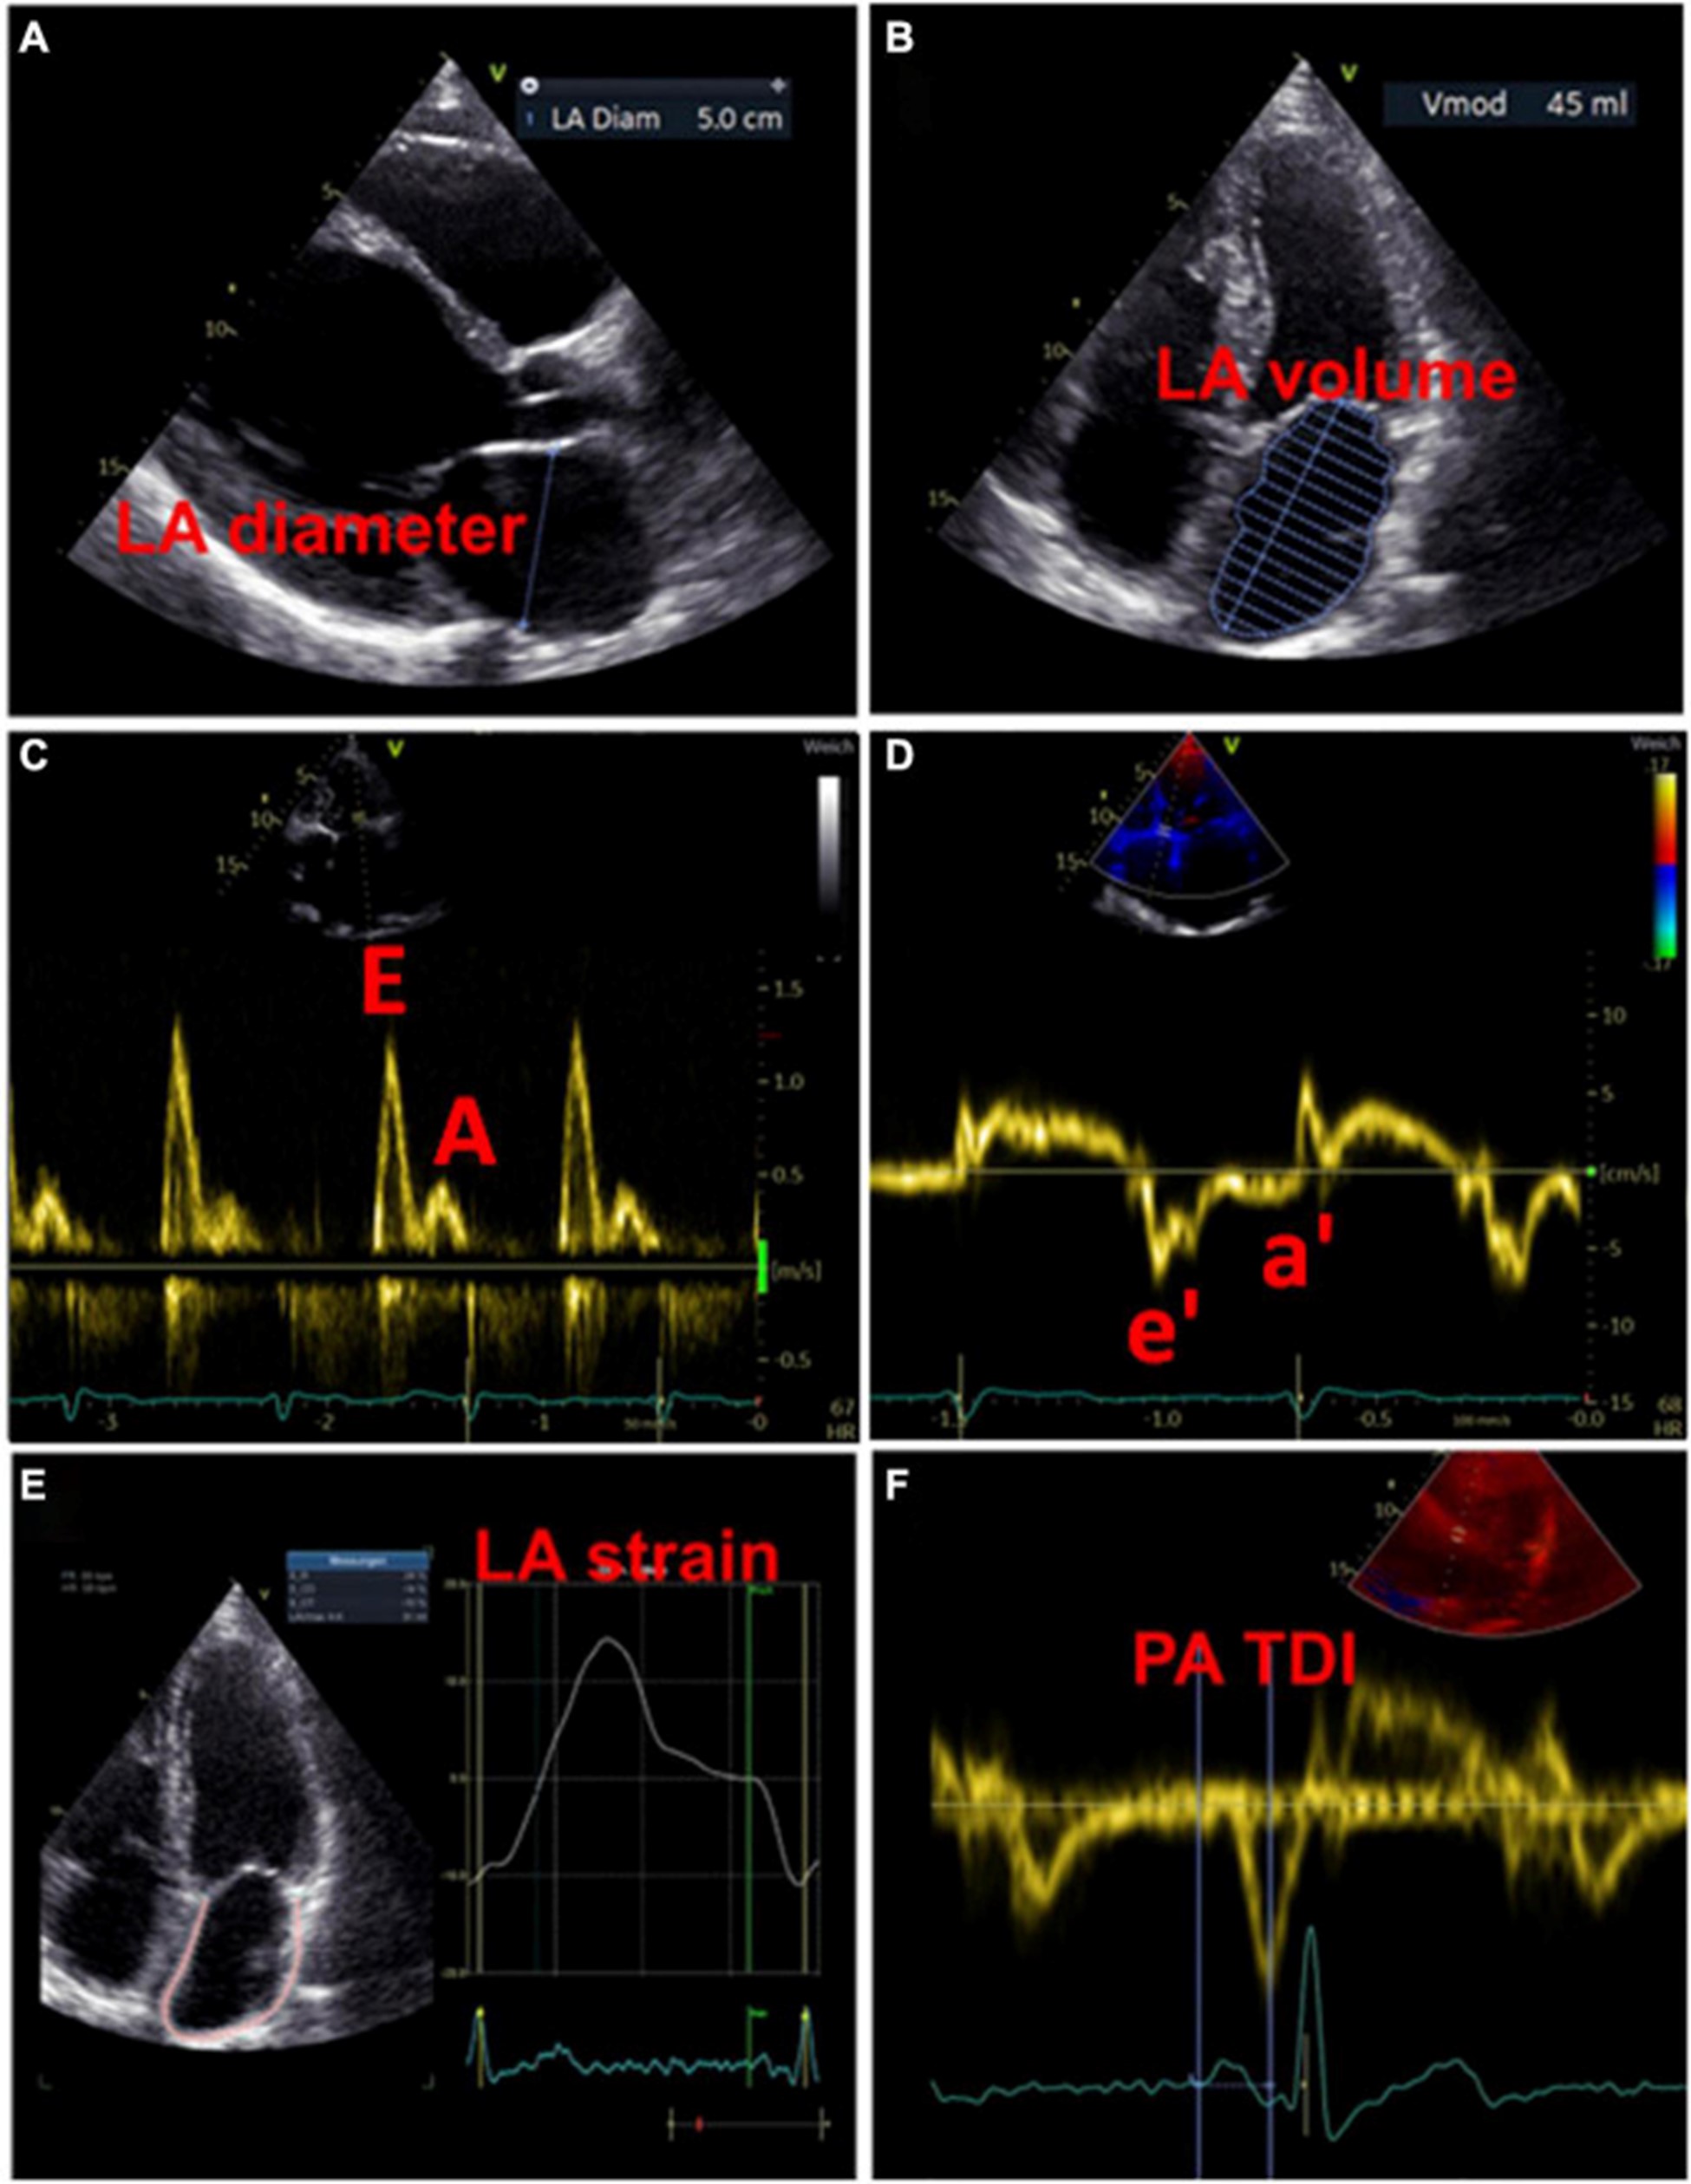

左心房大小

用于估计 LA 大小的一个广泛使用的参数是 LA 直径 (图 3A)。在 AFFIRM 研究中,增加的 LA 直径与复发性 AF 相关,但与卒中风险无关 。然而,一项荟萃分析揭示了较大的 LA 直径与中风和血栓栓塞事件的发生率之间存在关联 。此外,大 LA 直径和 LA 体积指数都被证明是主要不良心血管和血栓栓塞事件的预测参数,特别是在没有 AF 的年轻患者中 。LA 容积指数更精确,因此更适合估计心房大小(图 3B)。增加的 LA 体积指数已被描述为心肌功能障碍的潜在早期标志物,并且经常出现在 AF 患者中,在更高的 AF 负担中频率增加 。此外,与似乎没有预测作用的最大 LA 体积相比,最小 LA 体积与新发 AF 和主要不良心血管事件的发生率密切相关 ( 53 – 56 )。

图 3:用于检测左心房心肌病的超声心动图测量示例。(A)测量左心房舒张期的直径。(B)左心房舒张期左心房容积的测量。(C)左心室舒张期的经口流入曲线:第一波代表 E 波(血液被动流入左心室),第二波代表 A 波(左心房主动收缩)。(D)左心室心肌运动的组织多普勒成像,结合(C)心房功能和左心室舒张末期压力的测量结果。(五)左心房的应变分析。(F)测量从 P 波开始(作为心房电活动开始)到 a' 波峰值(心房收缩的机械反应)的 PA-TDI 间隔。

多普勒超声心动图

此外,可以通过脉冲波多普勒测量和组织多普勒成像来评估 LA 功能。LA 功能受损可能提示 LACM,在使用多普勒超声心动图的研究中,这与 AF 和 AF 负担等临床结果等同。表格1)。

过去,已经研究了许多与二尖瓣血流和舒张期心肌运动相关的超声心动图参数与 LA 功能和临床事件的关联 。然而,尚未确定适合诊断左心房心肌病的参数和相应的临界值。

虽然 LA 传导功能(以二尖瓣 E 波速度为代表)随着 AF 负荷的增加而增加,但 LA 收缩功能(以二尖瓣 A 波速度和二尖瓣环组织多普勒 a' 速度为代表)具有相反的效果。

。早期 [E] 和晚期 [A] 舒张期充盈波的比率增加与 AF 风险之间存在关联。此外,描述了峰值 A 波速度和 AF 风险之间的 U 形关系 。

二尖瓣环“e”波速度降低和 E/e 比增加表明左室舒张功能受损。有证据表明后一个参数也适用于评估 LA 功能和压力 (图 3C、D)。

通过组织多普勒成像持续时间评估的总心房传导时间

通过组织多普勒成像持续时间评估的总心房传导时间,代表超声心动图得出的总心房传导时间,是结构和电心房重塑的吉祥标志,在窦性心律期间测量为 P 波开始之间的时间间隔在表面心电图上的导联 II 和超声心动图上左室侧壁的组织多普勒成像 (TDI) 跟踪上的 A' 波峰值 (图 3F)。PA-TDI 持续时间延长与节律控制干预后新发 AF、术后 AF 和 AF 复发相关 。在 AF 患者中,血栓栓塞风险的评估通过增加 PA-TDI 持续时间值得到改善。迄今为止,尚未建立 PA-TDI 持续时间的标准参考值。然而,如果每个超声心动图实验室通过常规获取 PA-TDI 值来确定自己的正常值,则可能会改善对 AF 相关结果的风险评估 。

斑点追踪超声心动图

近年来,斑点追踪超声心动图已成为通过评估组织运动来检测早期心肌变形的流行方法 。LA 应变和应变率成像提供了对心房功能重塑的见解。图 3E)。评估斑点追踪超声心动图效用的研究主要通过临床定义(例如,AF、AF 负担、AF 复发、血栓栓塞事件)或通过与电解剖标测中的异常发现进行比较来定义 LACM。表格1)。